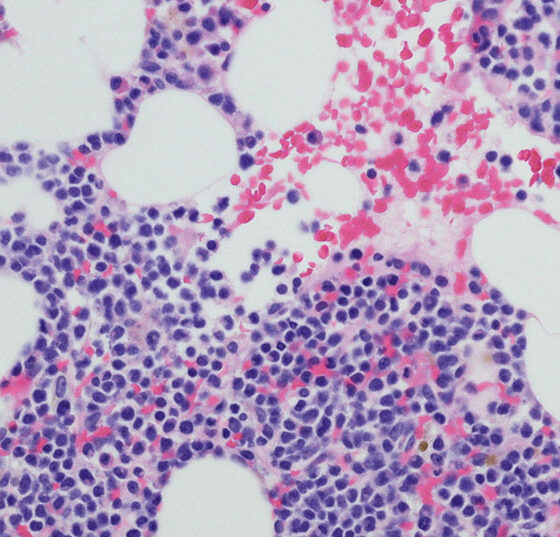

• Multiples Myelom (MM)

Prognostische Faktoren, die Rolle von Leptin und MGUS im Fokus

Das Multiple Myelom entsteht durch die Entartung einer einzigen Plasmazelle, deren Klone sich im Knochenmark ausbreiten. Insgesamt tritt die Erkrankung nur sehr selten auf. Allerdings gehört sie zu den häufigsten...…